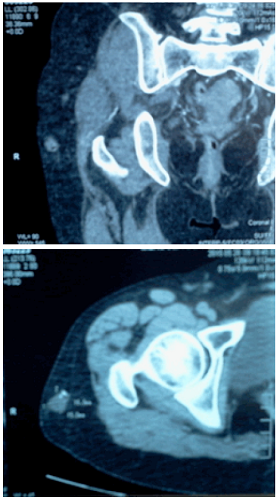

La Figura 2 corresponde a una TAC de muslo derecho con contraste en la que se evidencia presencia de nódulo sólido de bordes definidos de 17x16mm localizado en el espesor de tejido celular subcutáneo de la cara anterolateral del muslo proximal. El nódulo no infiltra los planos musculares superficiales ni profundos

Tras la administración de contraste, se evidencia refuerzo heterogéneo. La Figura 3 corresponde a una TAC en la que no se evidencia adenopatías perirregionales y el muslo izquierdo se encuentra sin alteraciones